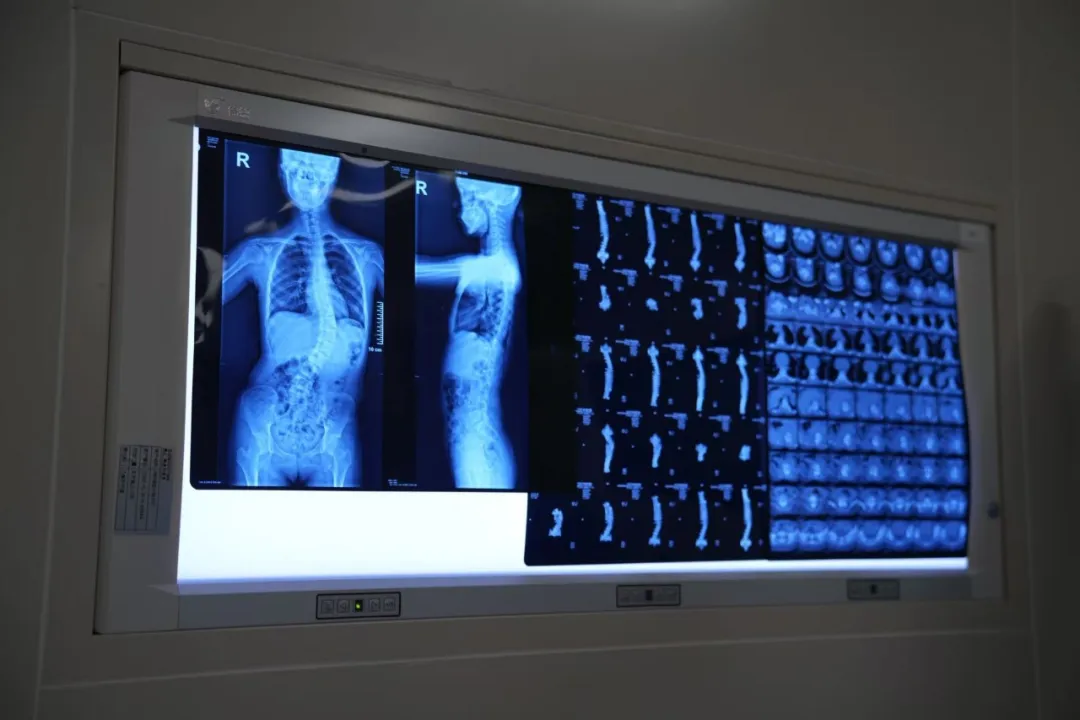

患者术前确诊脊柱侧弯8个月,脊柱呈S形畸形:胸椎左侧弯Cobb角约20°,腰椎右侧弯Cobb角约42°,伴有双肩不等高、胸廓不对称、肋骨突出等症状,已严重影响身心健康。

脊柱矫正手术因紧邻中枢脊髓与胸腹大血管,对三维矫形精度要求较高,围术期需多系统协同保障。全国能够独立开展此类复杂脊柱矫正手术的医院较为有限。